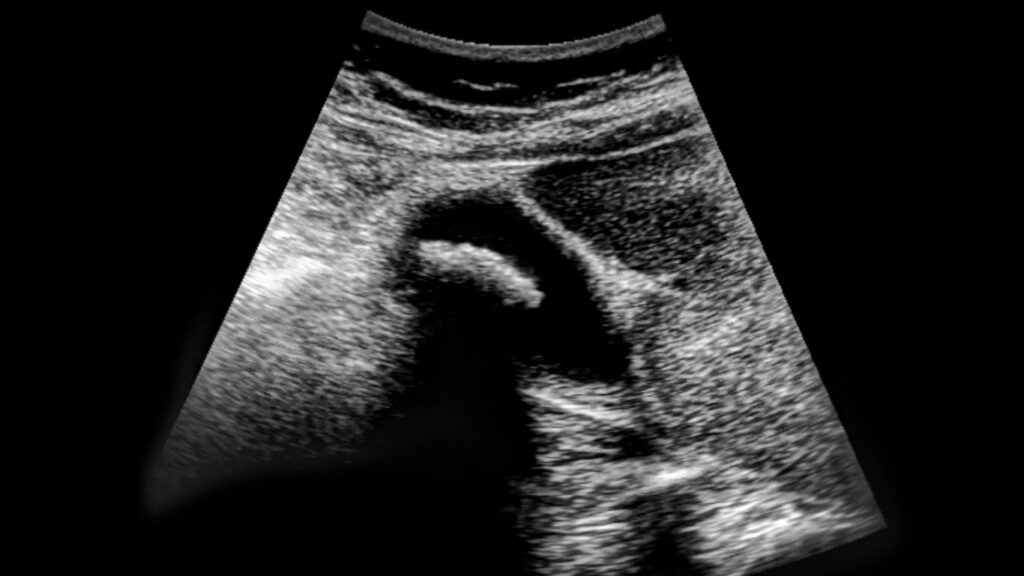

Ecografías Obstétricas: Cuidado y Precisión en Querétaro

En Altaria, nos dedicamos a proporcionar una atención excepcional en ecografías obstétricas, centrada en el bienestar de la madre y el bebé. Nuestro equipo cuenta con una sólida formación en medicina materno-fetal, lo que nos permite ofrecer un seguimiento detallado durante el embarazo. Utilizamos tecnología de última generación en nuestro centro de ecografías, garantizando precisión […]